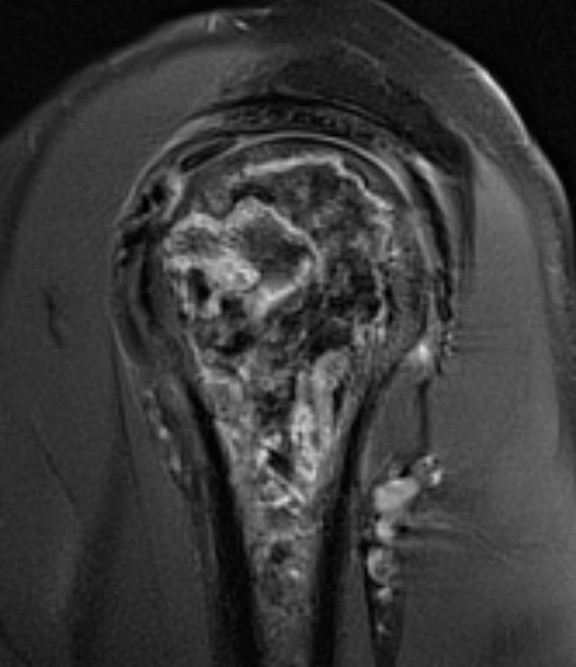

Classification / Cruess modification of Ficat-Arlet

Stage I - pre-xray change / diagnosed on MRI

Stage II - sphericity maintained / sclerotic changes in superior central head / crescent sign

Stage III - mild flattening articular surface

Stage IV - significant humeral collapse with loss integrity joint surface

Stage V - degeneration extends to involve glenoid

MRI

Sensitivity and specificity approach 100%

T1

- areas low signal intensity on T1 representing edema

- areas of high signal intensity thought to represent blood flow

T2

"Double line sign"

- highly specific for AVN

- inner bright line representing granulation tissue

- outer dark line representing sclerotic bone